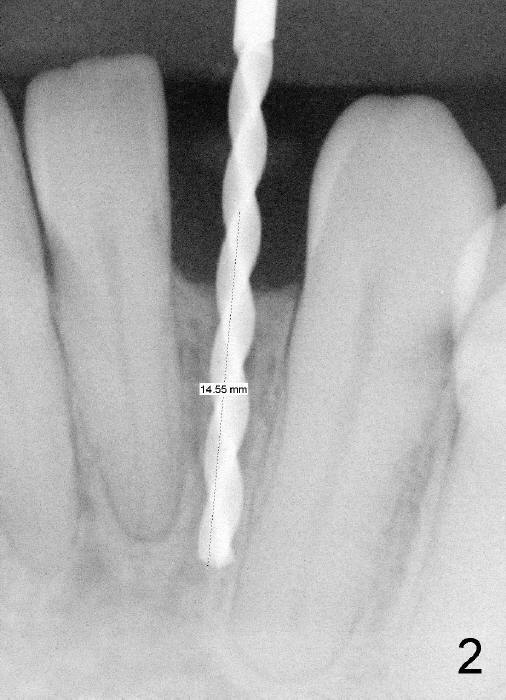

Informed consent is obtained with emphasis of potential damage to the neighboring roots. Two PAs have to be taken with the first pilot drill (1.5 mm) in place for determination of initial trajectory (Fig.2,3). Osteotomy is enlarged coronally with 2 mm pilot drill. Finally a 3x17 mm one piece implant is placed with primary stability, determined tactilely (Fig.4). Immediate provisional is fabricated. To avoid micromovement, the immediate provisional (Fig.5 P) is bonded to the neighboring teeth with composite (*); it is further fixed in place with a lingual retainer (Fig.6 arrowhead).